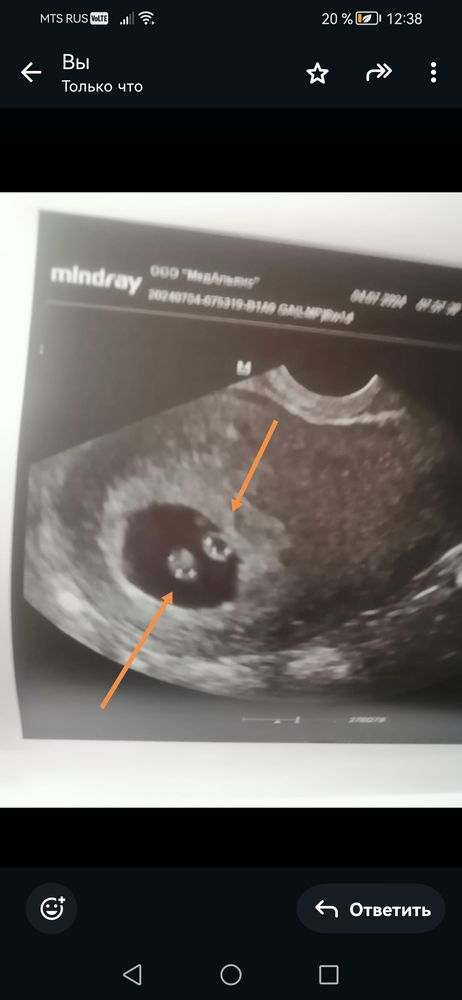

6+4 Изображение

ИРА2010, это двойняшки ? Два плодных яйца?

Валерия, да,ди ди

ИРА2010, у вас двойняшки не близнецы. У автора близнецы однляйцевые

Little Koldynia, нет в медицине такого термина-двойняшки, это народное название. У ИРА2010 разнояйцевые близнецы.